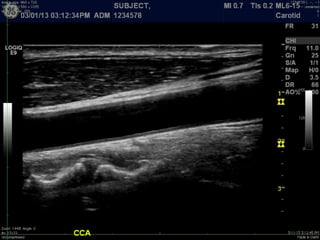

B-mode, 2D imaging

A Primer ofDiagnostic Ultrasonic Imaging Modalities B-mode, 2D imaging